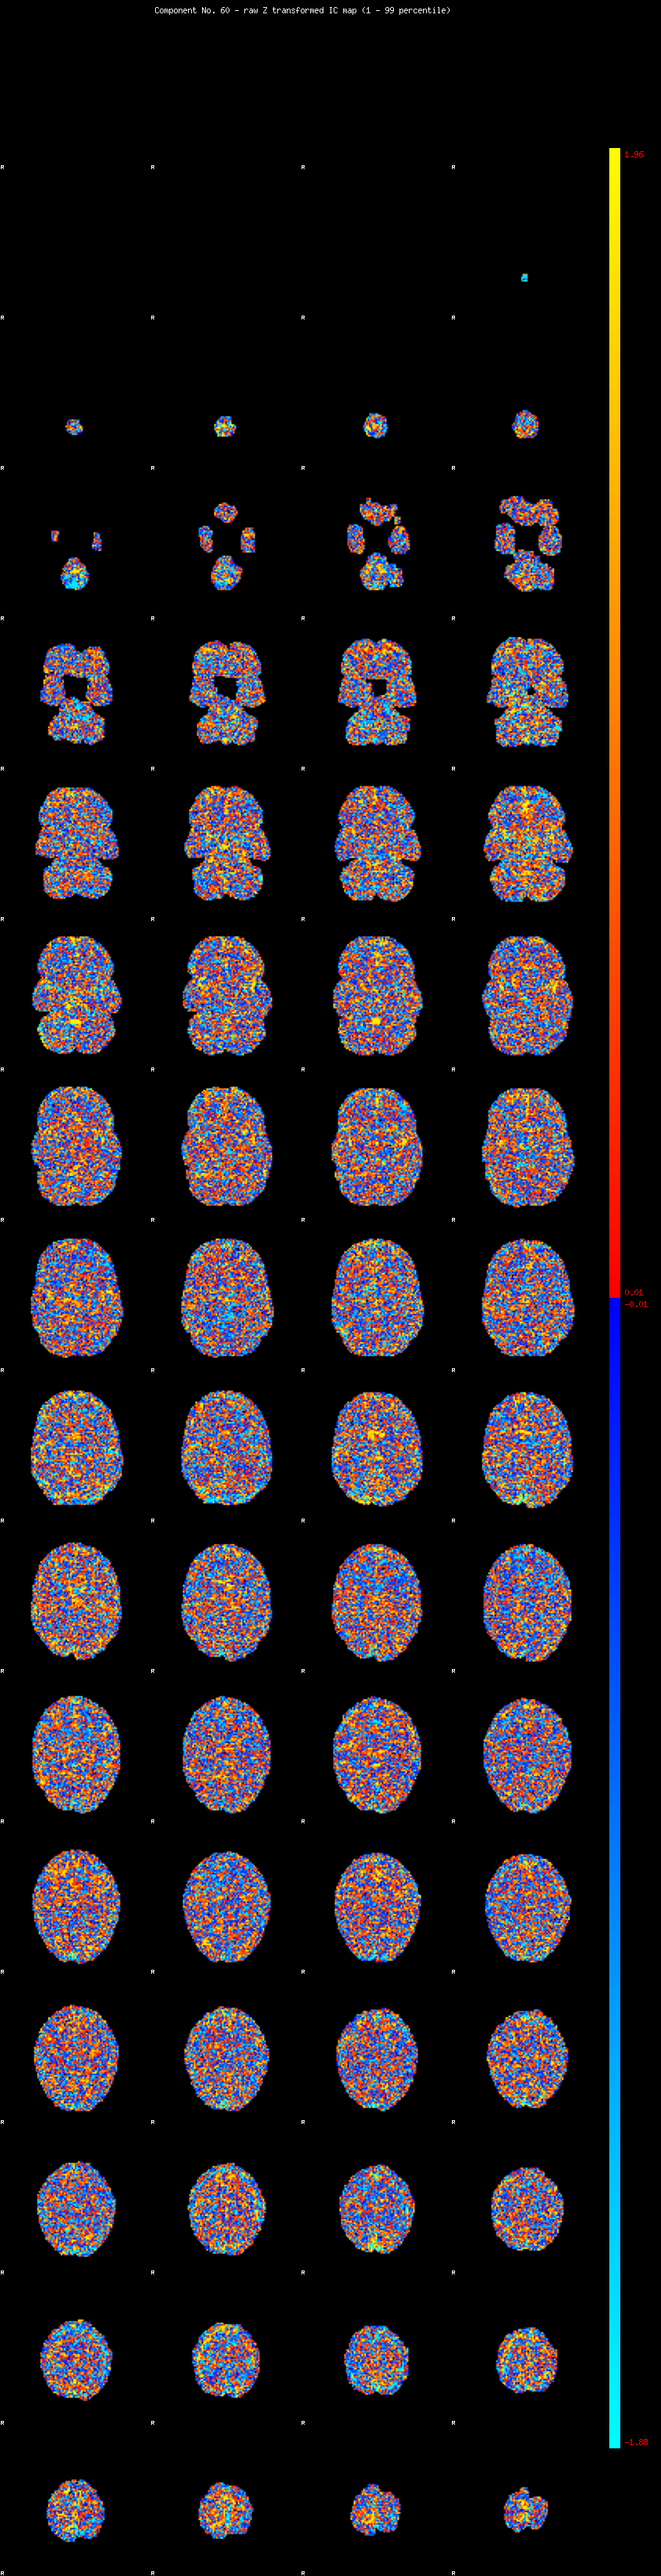

IC_60 Mixture Model fit

Means : -0.000000 2.124275 -2.074611

Vars : 1.000000 0.976137 0.854406

Prop. : 0.940605 0.034981 0.024414